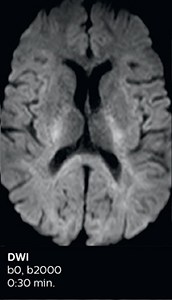

Fast acute stroke protocol

This is an example of acute ischemic stroke with distal occlusion of the right posterior cerebral artery. Note the improved visibility of the ischemic territory on the diffusion weighted image with high b-value. The 3D FLAIR shows a distal PCA occlusion. The fast SWIp depicts the thrombus on the isolated second echo image. The total scan time (including SmartBrain, preparations and a fast 3D T1w TSE Gd) is 8:00 minutes.

Improved diffusion imaging in stroke patients

Using MultiBand SENSE allowed the staff to improve their diffusion quality. “Our diffusion sequence was already fast before, about 40 seconds. Now with Elition, it still lasts 40 seconds, but we improved the spatial resolution by 0.2 mm and use high b-values to be more sensitive to visualize changes related to acute stroke,” says Dr. Savatovsky.